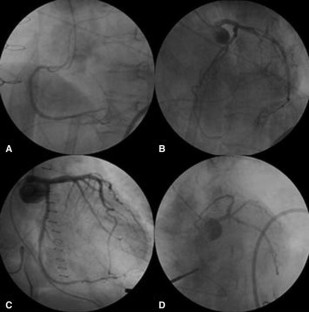

A 75-year-old female was admitted to our hospital with sudden back pain and right leg ischemia. Computed tomography showed acute type A aortic dissection with the occlusion of the right common iliac artery. The patient was treated with ascending aorta replacement and femoro-femoral bypass. Three hours after the operation, the patient went into a sudden shock. Electrocardiogram showed ventricular tachycardia and ventricular fibrillation. Percutaneous cardio-pulmonary support was administered and coronary arteriogram (CAG) was proceeded for evaluation of the coronary arteries. Although CAG revealed normal coronary arteries, intravascular ultrasound showed mobile intimal flap at left main coronary artery trunk, suggesting dissection of the coronary artery. Percutaneous coronary intervention of the left main coronary artery trunk was performed. The patient recovered from shock and was discharged from the hospital without any major complication.

Fig. 4